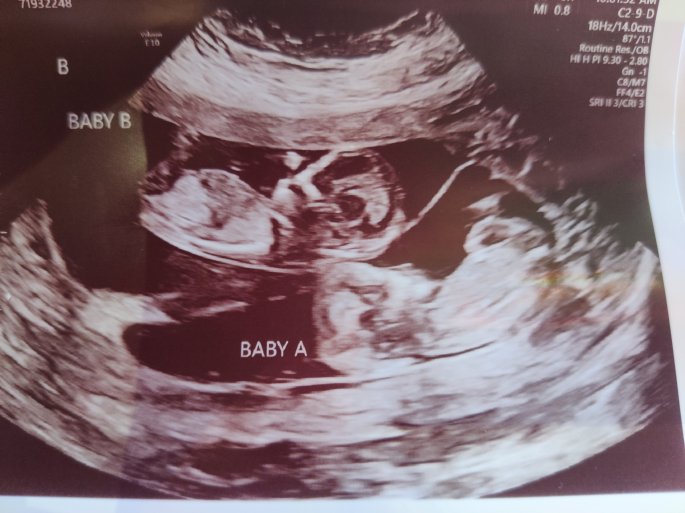

September I started bleeding and just knew I was having a miscarriage. I dropped my daughter off at school (all while trying not to sob because I didn’t want her to know anything- and I am an idiot because she obviously did)and headed straight up to the ER with my husband. They weren’t going to let him in with me because of covid restrictions and I freaked out a little bit and told them that I was having a miscarriage and I needed him there, so they let him come back. I had an ultrasound and blood work done and the doc comes back and in and was like “did you know you weren’t having twins??” then goes on to talk about twins and pregnancy and all of that. I am bawling my eyes out because now I am thinking I just miscarried twins!!! And then the doc was like “they both have heartbeats”. I just started laughing. I was so so so happy! I called my midwife once I was discharged to let them know what was going on and once I told them it was twins, they let me know that I am considered high risk and that they can no longer have me as a patient. So I had to find a new doc. Which I did.

During this time I had a follow-up ultrasound done because the US tech at the hospital saw something they didn’t think was just right… With baby B the gap between the base of the neck and the lining of the sac was bigger than it is supposed to be. With the gap the size that it is, there is a 50% chance that there could be something wrong. Luckily a few weeks later I got the test results for the blood work and everything turned out ok with that. There were a few other tests that I needed to do, but in the end, everything turned out perfect!!